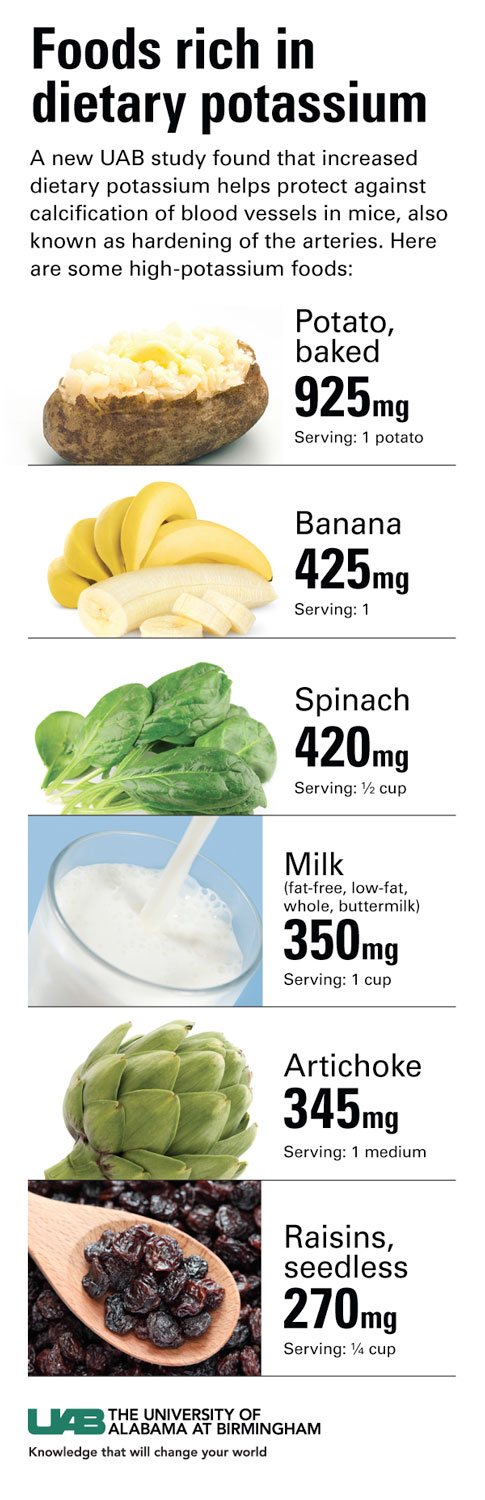

Using natural treatments such as ginger juice is your answer for how to get rid of calcium deposits by bringing down the inflammation and pain. The scientists also found that. As such, loading your diet with calcium may actually prevent calcium buildup in your arteries.

Aortic valve calcification may be an early sign of heart disease, even if there aren't any other heart disease symptoms. Water filters like ion exchange or reverse osmosis can remove up to 98% of the impurities in hard water, so technically, they can get rid of the calcium, but not all of it. A great and easy way to prevent calcium buildup is by applying a calcium prohibitor or blockerto the pool tiles or glass.